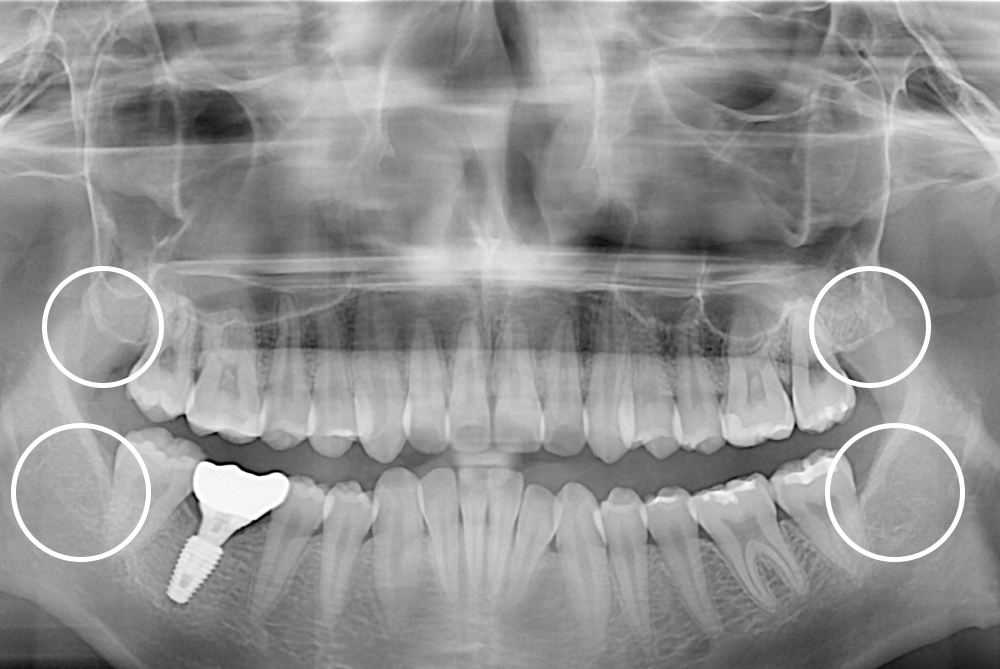

[사랑니] 매복 사랑니 발치

치료전 : 2020-06-10

세종치과는 구강악안면외과학 박사이신 원장님이 발치하는 치과입니다.